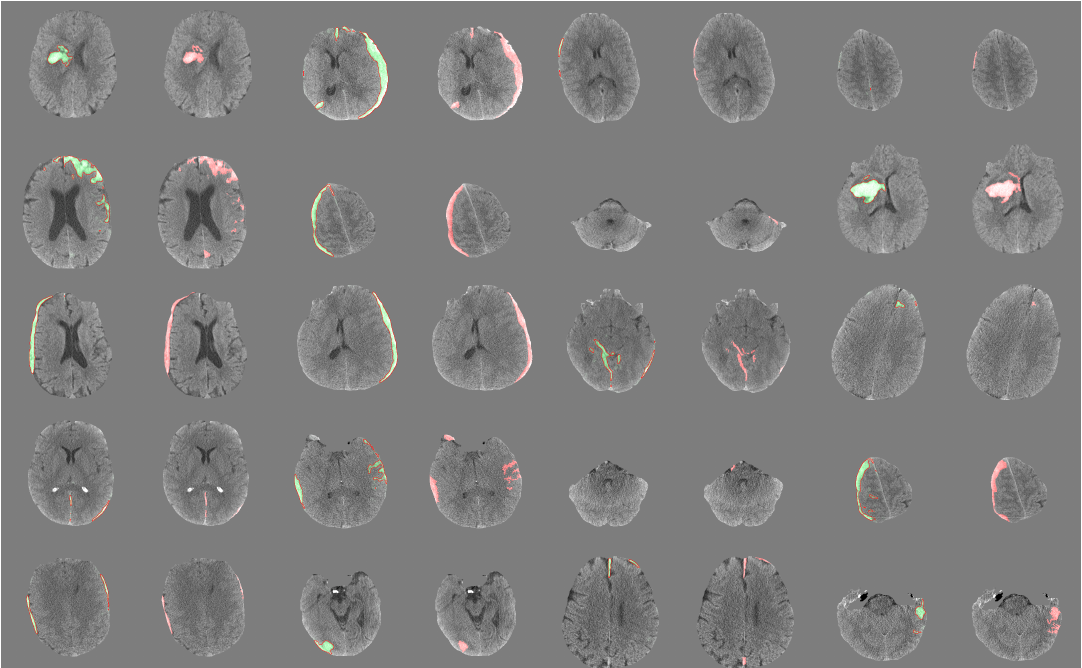

- Bone extraction: Skull and Face were removed from CT images to retain only the intracranial structures.

PatchFCN

On the previous paper, PatchFCN for Intracranial Hemorrhage Detection found patch-based FCN outperforms FCN by finding an optimal trade-off between batch diversity and the amount of context.

sliding window 기반의 방법을 이용하여 inference 하며